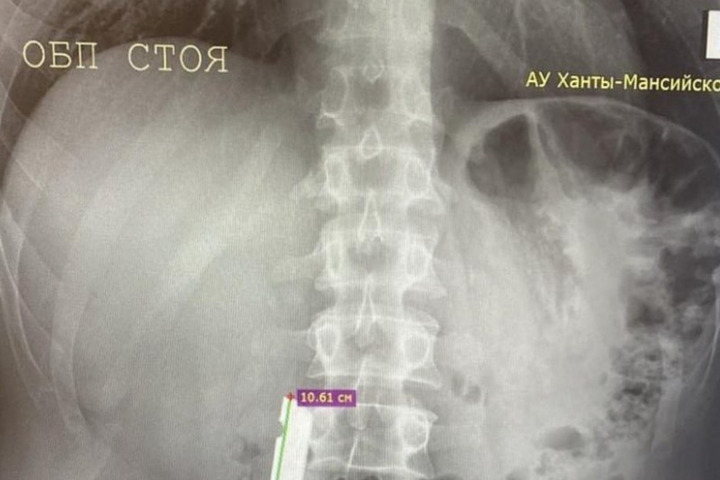

Врачи Советской районной больницы совершили успешное хирургическое вмешательство, в ходе которого извлекли крупное металлическое инородное тело из двенадцатиперстной кишки пациента. История началась с поступления больного, у которого при рентгенографическом обследовании было обнаружено постороннее тело в верхних отделах желудочно-кишечного тракта.

Экстренная диагностика с помощью эзофагогастродуоденоскопии (ЭГДС) позволила точно определить местоположение металлического предмета — он находился в двенадцатиперстной кишке. На первом этапе операции специалистам удалось переместить инородное тело в желудок, однако дальнейшие попытки его извлечения не принесли желаемого результата.

Заведующий хирургическим отделением Иван Папалуца отметил особую сложность проведённой операции. По его словам, трудности были связаны с крупными размерами инородного тела, его специфическим расположением и острыми краями, которые затрудняли манипуляцию инструментами. Успех операции, по мнению врача, стал возможен благодаря двум ключевым факторам: наличию круглосуточной эндоскопической службы, позволяющей оказывать помощь пациентам в кратчайшие сроки, и слаженной командной работе медицинского персонала. Особую благодарность заведующий отделением выразил медицинским сёстрам Марине Гатиятовой и Галине Поповой за их профессионализм и помощь в проведении операции.